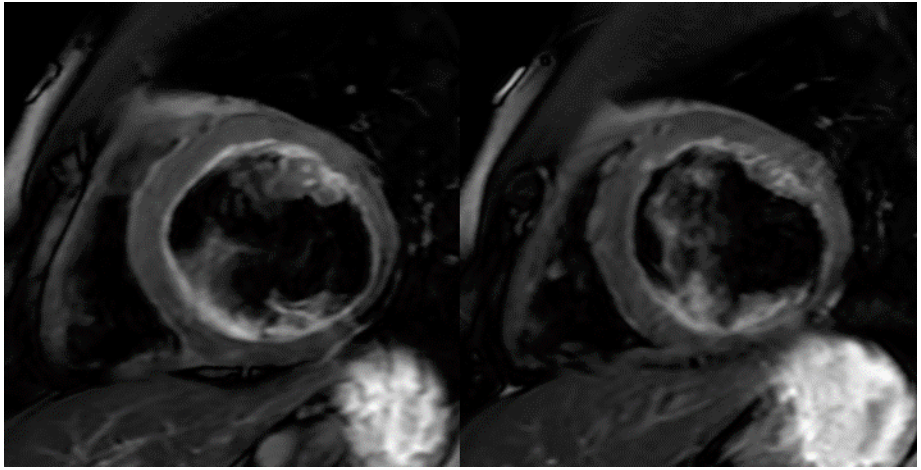

SA 和 4CH PSMDE(DL Recon)提示患者下侧壁、下壁和下间隔壁透壁性心肌梗死;除此之外,乳头肌出现显著的延迟强化,这应该提示乳头肌梗死。 至此,我们再大胆地复原一下该患者的病变过程: (1)一年前心衰症状出现;(2)病因为左心室下侧壁、下壁和下间隔壁透壁性心肌梗死,提示责任血管为LCX和RCA;(3)乳头肌梗死,导致二尖瓣关闭不全。 孙斌主任点评: 传统MR在信号采集过程中,无法区分真实的信号和噪声。所以,为了提升SNR和CNR,往往用最笨的方法:多NEX堆。费时费力,患者体验差,医院流通量上不去。DL打破传统傅里叶变换重建的魔咒,在原始数据空间进行噪声分离,只保留最纯真的MR信号。不但可以大幅提升SNR,还可以有效增强CNR,让微小病变和正常组织之间的差异最大化,为诊断提供最有效的助力。